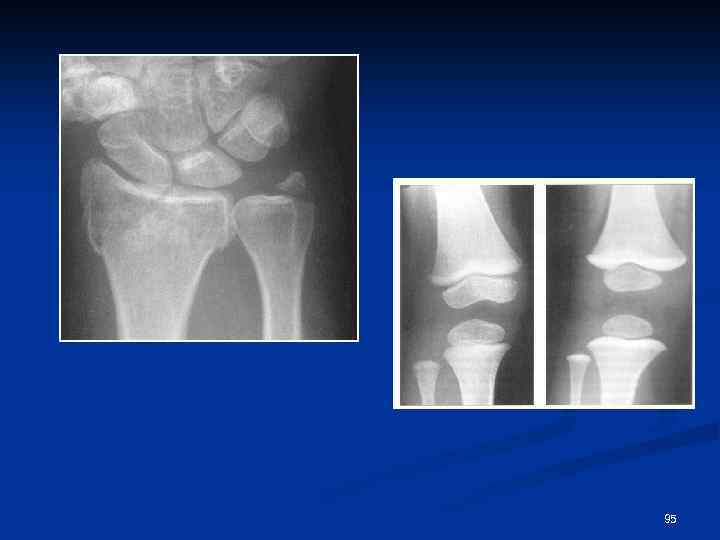

Особенности переломов у детей n n n Эпифизеолиз Поднадкостничные переломы Переломы по типу «зеленой веточки» 93

94

95